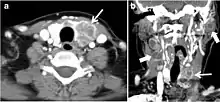

Fig. 5. A poorly differentiated invasive left thyroid mass in a 58-year-old female patient. a Sagittal greyscale neck ultrasound shows a large hypoechoic lesion with macro-calcification and micro-calcification. b Sagittal colour Doppler ultrasound shows left internal jugular vein filling defect with detected internal vascularity suggestive of tumour thrombus. c Enhanced axial and coronal CT scans of the neck show heterogeneously enhancing large lesion replacing the left thyroid lobe and extending to the isthmus and the medial aspect of the right thyroid lobe (white arrow). The mass and the conglomerate lymph nodes measure 12.5 × 7 × 5.8 cm (white arrows). d, e Axial enhanced CT scans show enlarged left cervical nodes (white arrow) and left internal jugular vein (IJV) thrombus (black arrows). Note the IJV distention and central enhancing portion in the upper cut (black arrow in e) concerning the tumour thrombus. f, g Enhanced axial CT scan of the upper chest demonstrate a mass extension into the retrosternal area, left tracheoesophageal groove, and posterior to the trachea (white arrows in f). There are multiple bilateral pulmonary nodules (white arrows in g).[1]

Surgery is the primary mode of treatment for DTCs. Post total thyroidectomy radioactive iodine (RAI) ablation is an option, especially in patients with distant metastasis, tumours larger than 4 cm, or extra-thyroidal disease extension. Ultrasound examination is usually adequate in evaluating primary tumours and cervical lymph nodes. Preoperative cross-sectional imaging with CT or MRI is indicated if there is a concern for local invasion that may alter the patient's staging as well as surgical approach (Figs. 4, 55 and 6)6) . Some thyroid primaries may be small, diffuse, or multifocal and therefore may be occult on imaging (Fig. 4) .[1]

The radiologist must evaluate the central structures draping the thyroid gland including the trachea, oesophagus, larynx, and pharynx, as well as the recurrent laryngeal nerve. Invasion is suspected if the thyroid mass abuts the airway or oesophagus for more than 180 degrees. Luminal deformity, mucosal thickening and mucosal focal irregularity are more specific indicators of invasion. Obliteration of the fat planes of the tracheoesophageal groove in three axial images and signs of vocal cord paralysis are indicative of recurrent laryngeal nerve invasion. Invasion of these central structures meets the criteria for T4a disease (Figs. 5 and and6)6).[1]

Arterial invasion constitutes T4b disease, which may preclude curative surgery. More than 180 degrees of arterial encasement is suggestive of invasion, however, arterial deformity or narrowing is much more suspicious for invasion. The carotid artery is the most commonly involved artery; however, the mediastinal vessels should also be examined. Encasement of the carotid artery or mediastinal vessels for more than 270 degrees is unlikely to be resectable. On the other hand, occlusion or effacement of the internal jugular vein can occur without invasion and does not influence surgical resectability or staging. Asymmetry of the strap muscle and the tumour abutting its external surface are signs of an invasion. However, invasion of the pre-vertebral musculature is more challenging, as a large lesion can compress the muscle without invasion (Figs. 5 and and6)6).[1]

Finally, the possibility of metastatic disease should be excluded. PTCs and medullary thyroid carcinomas tend to metastasize to regional lymph nodes. According to the AJCC/UICC TNM staging system, the nodal stage is classified by site: N1a indicates level VI nodal involvement, including paratracheal nodes; N1b indicates unilateral or bilateral lateral cervical nodal disease or superior mediastinal nodal disease (Figs. 4, 55 and and6)6).[1]